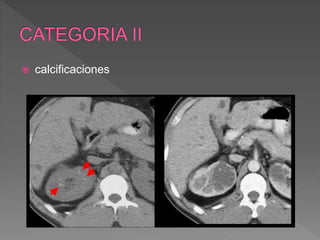

 calcificaciones

 Hallazgos:

› Finos tabiques<1mm

realzan suavemente

› Pequeñas calcificaciones

finas en la pared o en los

tabiques

 Mínimamente complicados

 No requieren intervención

quirurgica

 Deben ser controlados

 Mínimo riesgo de

malignidad